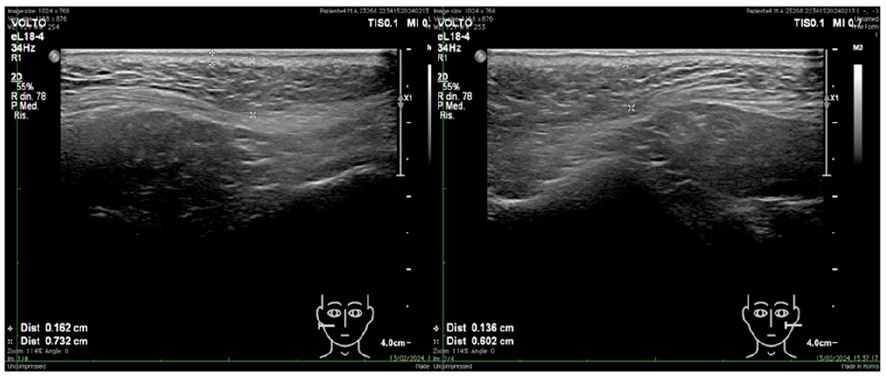

A targeted high-resolution ultrasound analysis was performed using Philips EPIQ Elite with «nSight Imaging» and ElastQ Imaging technology for shear wave elastography.

The transducer used was PureWave Crystal Technology eL18-4 Matrix Array, with a frequency range of 2 MHz to 22 MHz.

• Morphological assessment: High-frequency (18 MHz) transversal scans at the cheek level, parallel to the mandibular branch, evaluating dermal and hypodermal thickness (Figure 1).

Figure 1: Ultrasound morphological assessment. High-frequency (18 MHz) transversal scans at the cheek level, parallel to the mandibular branch, evaluating dermal and hypodermal thickness.